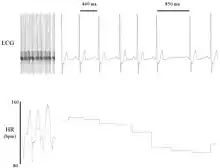

Heart rate variability (HRV) is the physiological phenomenon of variation in the time interval between heartbeats. It is measured by the variation in the beat-to-beat interval.

Other terms used include "cycle length variability", "R–R variability" (where R is a point corresponding to the peak of the QRS complex of the ECG wave; and RR is the interval between successive Rs), and "heart period variability".

Variation in the beat-to-beat interval is a physiological phenomenon. The SA node receives several different inputs and the instantaneous heart rate or RR interval and its variation are the results of these inputs.